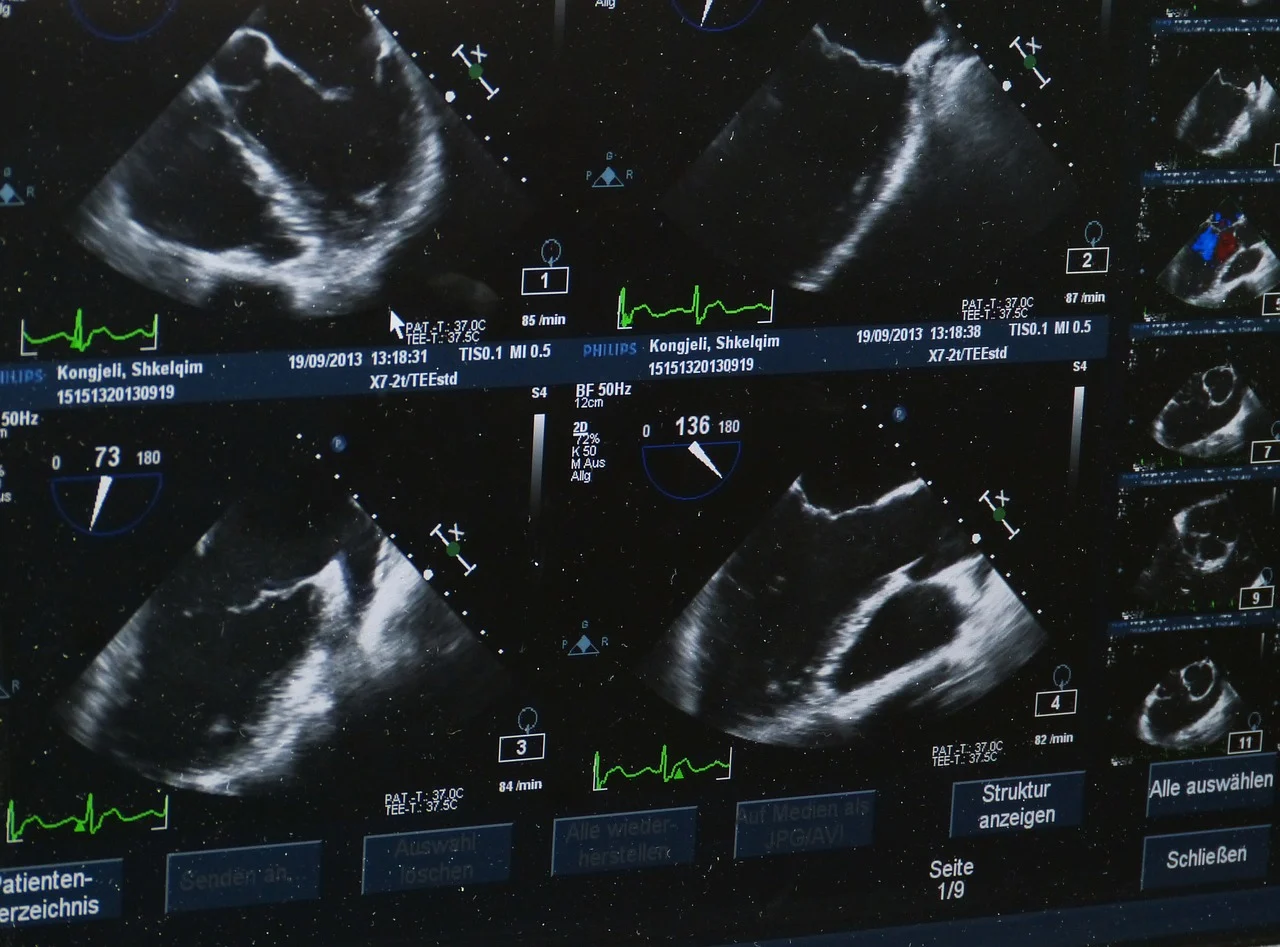

심장초음파, 골밀도 검사, 호르몬 검사, 관절염 검사, 안저 검사

전립선 초음파, 뇌혈류검사, 심창초음파, 골밀도검사, 호르몬 검사, 관러염 검사, 안저 검사